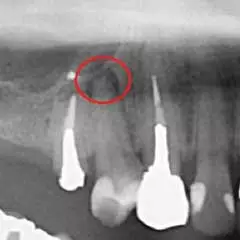

CTはマイクロスコープ(歯科用顕微鏡)同様、治療部位を「見える化」させる機器です。通常のレントゲン(デンタルエックス線写真)でも大まかには判断可能ですが、CTを用いる事で、デンタルエックス線写真では発見できないような微細な病変も発見することが出来ます。

赤丸部分が問題の個所になりますが、一般的なレントゲンではしっかりと確認することは出来ませんが、

治療をする上で、最初の診査診断が非常に重要となります。

なぜなら、最初の段階で正確な診断を下さなければ、誤った治療法を選択し、最終的には残せる歯も残せなくなる恐れがあるためです。

当院では「見える化」できるCTを活用し、誤った診査診断を回避するための細心の注意を払っております。

CT画像

レントゲン画像